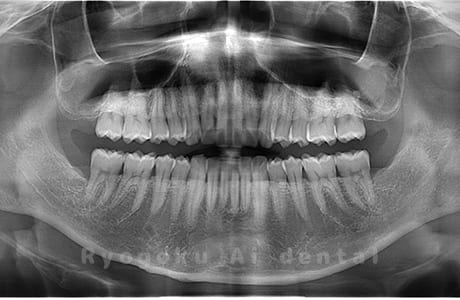

Case04

- 原因

- 上顎の親知らず、下顎の水平埋伏の親知らず

- 治療内容

- 上顎の親知らず、下顎の水平埋伏の親知らずを抜歯したケースです。

<リスク・副作用>

手術後は痛み、腫れ、痺れなどの副作用が生じる場合があります。